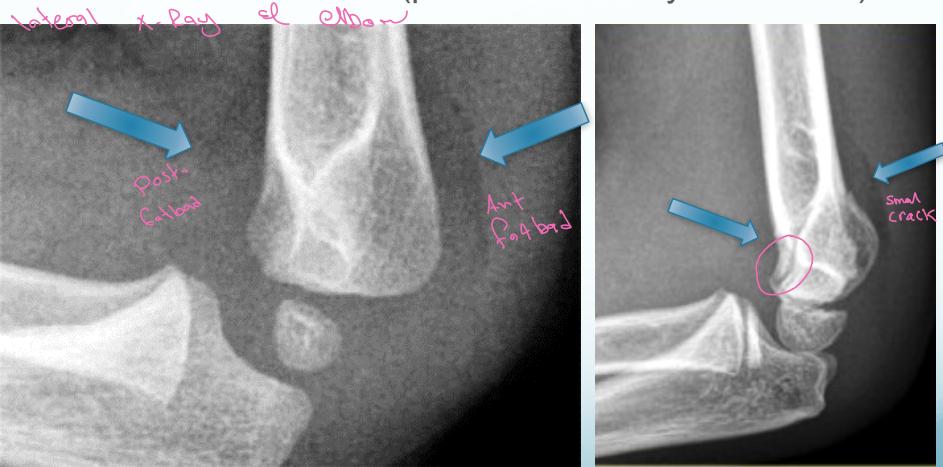

Lateral elbow X-ray image

- Fat pad sign:

- Indicates a fracture (posterior is always abnormal)

Anterior Humeral Line:

- A line drawn on a lateral view along the anterior surface of the humerus should pass through the middle third of the capitellum

Normal

Abnormal - Displaced posteriorly